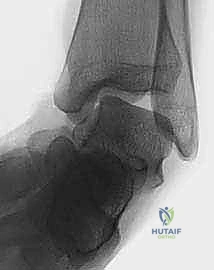

* الأشعة السينية (X-rays) مع الإجهاد: لاستبعاد الكسور وتقييم زوايا عدم الاستقرار.

* الرنين المغناطيسي (MRI): وهو الفحص الذهبي لرؤية الأنسجة الرخوة، وتحديد حجم التمزق في الأربطة، والتأكد من عدم وجود إصابات غضروفية مرافقة (Osteochondral defects).